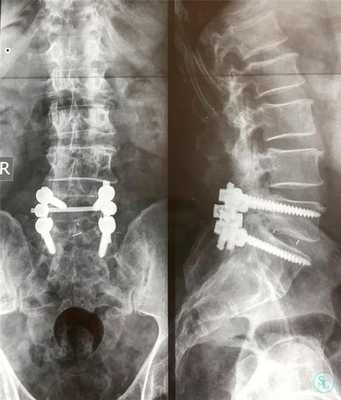

Транспедикулярная фиксация или ТПФ - операция, при которой позвонки фиксируются и стабилизируются при помощи специальных имплантов (транспедикулярных винтов). В каждом позвонке есть точка ввода винта, которую установил в 1985 году Рой Камилл — это точка пересечения поперечного отростка позвонка с верхнем суставным отростком. С помощью специальных инструментов в эту точку, вкручиваются винты определяя анатомически правильное расположение позвоночника, тем самым излечивая заболевание. Первые попытки установки имплантов были в 60-70 гг. прошлого века и с тех пор является «золотым стандартом» в лечения переломов и различных заболеваний позвоночника.

ТПФ выполняется под рентгеновским контролем, что позволяет хирургу точно контролировать каждое движение и избежать повреждения близкорасположенных анатомических структур. Чаще для этого используется ЭОП или КТ.

Очень важно при установки винтов соблюсти следующие моменты: отсутствие пространства между костью и винтом, исключение травматизации нервных и сосудистых структур или смежных дугоотросчатых суставов. Импланты устанавливаются согласно размерной линейки каждого позвонка и винта, бикортикально не касаясь замыкательных пластин.

Размер закрепляющих винтов для каждого больного подбирается индивидуально. Различают моноаксиальные и полиаксиальные винты, также разработаны варианты с боковой фиксацией стержня. Они вводятся по конвергентной монокортикальной методике, подразумевающей перфорацию позвонка только в точке входа винта.

Винты изготавливаются из титана, что гарантирует их высокую стойкость к различным деформирующим нагрузкам. Они оснащены поверхностными колпаками, обеспечивающими стабильность положения конструкции и ее защиту от перекоса. Все винты установленной системы объединяются специальными пружинистыми металлическими механизмами, что равномерно перераспределяет нагрузку на них.

Точка установки винта в корень дуги подбирается на основании расположения двух анатомических ориентиров - поперечного и суставного отростков позвонка. Непосредственно позвонок перфорируют с помощью специального зонда.

Практика показывает, что именно техника ТПФ имеет значительные преимущества над остальными при необходимости лечения переломов позвоночника. Она обеспечивает замыкание лишь короткого сегмента, перемещение в анатомически правильное положение и стабильную фиксацию за счет монтажа только одной конструкции. Это гарантирует возможность ранней мобилизации больного, при этом не требует внешней иммобилизации.

Нестабильность позвоночника считается одним из распространенных заболеваний и основным методом лечения является транспедикулярная фиксация подвижного сегмента, декомпрессивная ляминэктомия, дискэктомия с установкой между телами позвонков кейджа который фиксирует сегмент на 360 градусов (золотой стандарт). В подобных ситуациях метод обеспечивает надежный спондилодез у 80- 95% пациентов. ТПФ является одним из наиболее часто применяемых методов оперативного лечения заболеваний и травм в связи с тем, что современные хирурги стараются добиться спондилодеза на 360°. Достичь этого позволяет сочетание ТПФ с межтеловым спондилодезом, что обеспечивает высокую частоту костных сращений и отсутствие остаточной незначительной подвижности в передних отделах прооперированного сегмента. Поэтому при успешном завершении операции и правильном восстановлении пациенты гарантировано избавляются от болевого синдрома.